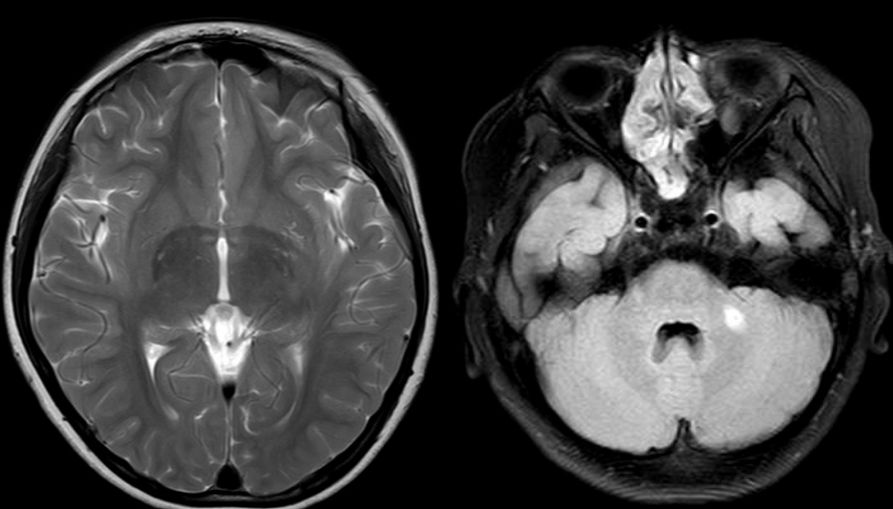

头颅MR:左侧小脑半球异常信号,左侧脑室体部后外侧异常信号,双侧半卵圆中心、侧脑室旁血管周围间隙增多。颈胸髓及腰骶部MRI提示:C3-T4平面脊髓肿胀,伴多发异常信号,胸髓全段肿胀,伴信号异常,腰骶髓异常信号影,考虑脊髓炎可能(图1)。

图1. 第一次住院头颅及脊髓MRI,显示左侧小脑半球异常信号。脊髓全段肿胀,伴信号异常,腰骶髓异常信号影,考虑脊髓炎可能。

图2. 治疗1年后复查头颅及全脊髓磁共振:左侧小脑半球与前片比较异常信号基本消失。全脊髓粗细正常,未见明显异常信号。